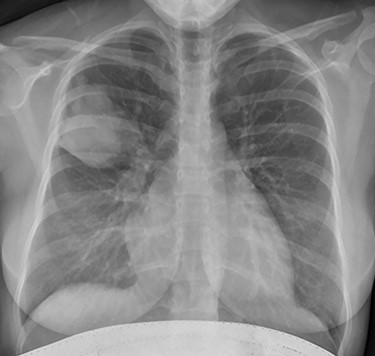

Initial investigations included a full blood panel with inflammatory markers (all within normal range) and a plain chest radiograph which demonstrated a mass in the right upper zone (Fig. 1). Computer tomography pulmonary angiogram (CTPA) scan demonstrated an 8 x 6.5 cm soft-tissue lesion within the right upper lobe (Fig. 2). This mass appeared to extend from the right hilum to the pleural surface and contained multiple small arterial branches. Her delivery date was brought forward pending further investigations. Positron emission tomography CT (PET-CT) demonstrated this lesion to be intensely fluorodeoxyglucose (FDG) avid (Fig. 3).

Aspergillus is a common environmental pathogen. However, clinically significant disease only occurs in a small proportion of patients. Although rare in its occurrence, it remains a considerable cause of morbidity and mortality in certain cohorts of patients. We describe a rare case of Aspergillus disease masquerading as a primary lung malignancy. Computer tomography pulmonary angiogram scan demonstrated a right upper lobe 8 x 6.5 cm soft-tissue lesion. Positron emission tomography CT demonstrated this lesion to be intensely fluorodeoxyglucose avid. Initial bronchoscopy demonstrated occluded subsegmental right upper lobe bronchus with white friable material. Follow-up bronchoscopy demonstrated evidence of a previous inflammatory process with cavitation and destruction of sub-lobar bronchial tree. Serial chest radiographs demonstrated almost complete resolution of the right upper lobe mass. Thus, this presentation of an Aspergillus-related lung mass masquerading as a primary lung malignancy provided several important learning points pertaining to diagnosis and ensuing management.